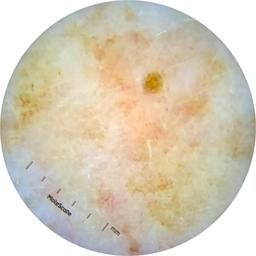

ISIC_9965024

Field Value

acquisition_day 129

age_approx 75

anatom_site_1 Head and neck

anatom_site_general head/neck

concomitant_biopsy False

diagnosis_1 Benign

diagnosis_confirm_type single image expert consensus

family_hx_mm False

image_manipulation instrument only

image_type dermoscopic

lesion_id IL_4355888

patient_id IP_7946204

personal_hx_mm True

sex female